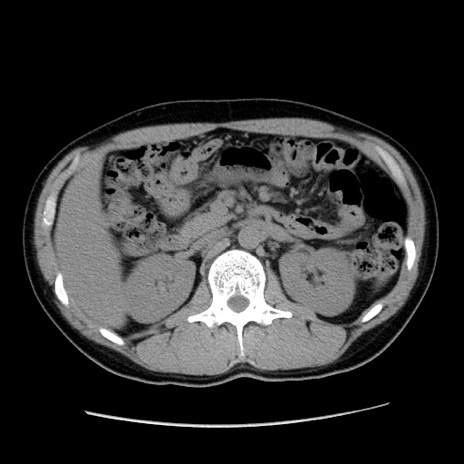

症例36(横断像)

【症例】20歳代 男性

【主訴】心窩部痛

【現病歴】今朝より上腹部痛あり。一旦軽快していたが再度出現したため救急要請。昨日夕に白身の魚を含む刺身を食べた。

【身体所見】BP 136/89mmHg、HR 74/min、BT 37.0℃、腹部:膨満、軟、心窩部に圧痛あり。反跳痛なし、筋性防御なし、腸雑音やや亢進あり。

【データ】WBC 17700、CRP 0.48